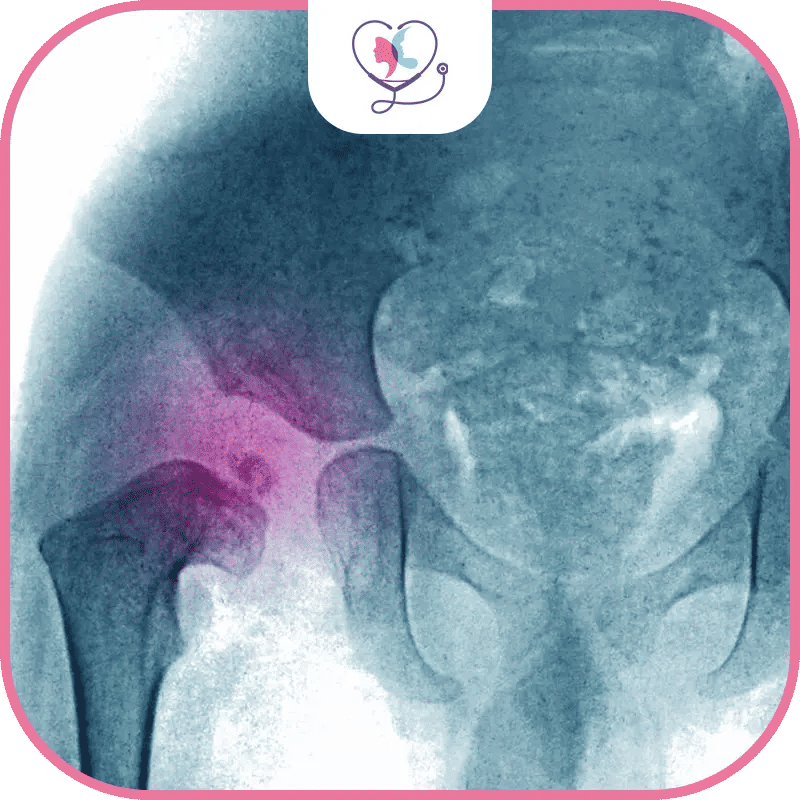

إنّ الخلع الولاديّ هو من أشيع التشوّهات الخلقيّة التي قد تصيب طفلك وتحتاج التدخّل العلاجيّ السريع للوقاية من المضاعفات السلبية في حال تأخّر العلاج، والخلع الولاديّ عند الرضّع هو خللٌ يؤثّر على تراكب رأس عظم الفخذ ضمن مفصل الورك لأسبابٍ مختلفة فد تكون وراثيّة أو الوضع المقعديّ أثناء الحمل.

في العموم تتراوح تكلفة عملية خلع الورك الولادي وجراحة العظام للأطفال مابين 3.000 $ - 12.000 $ حيث تتنوع الخيارات الجراحية المتاحة كـ التالي: